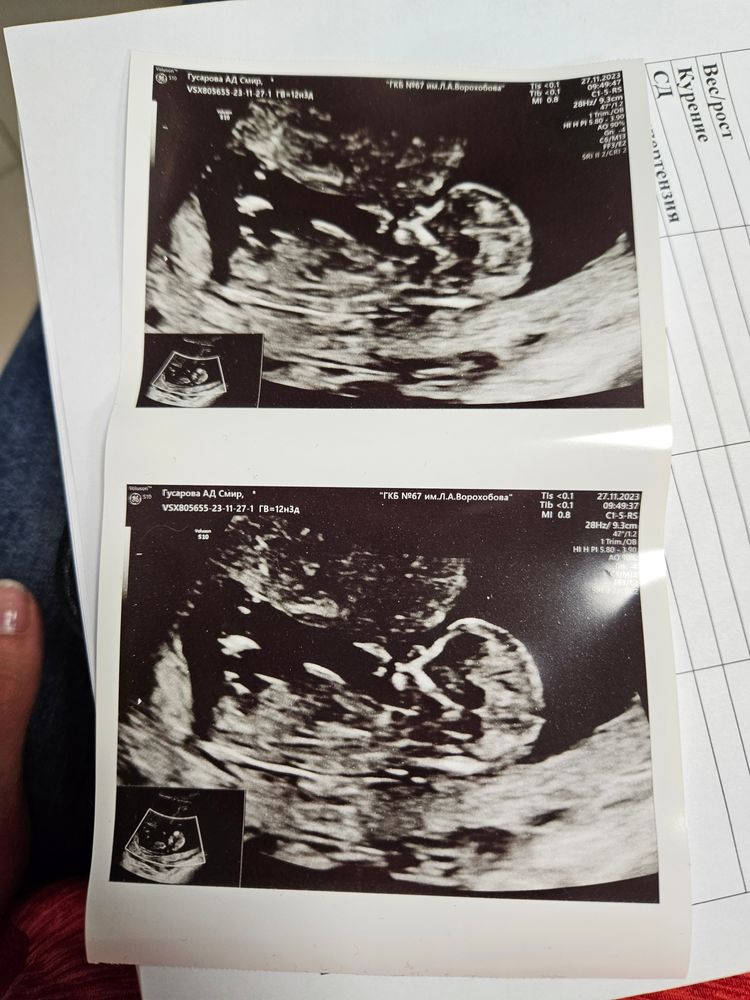

Такого доброго и трепетного отношения на УЗИ у меня ещё ни разу не было за все беременности. Такая отзывчивая девушка, так тщательно посмотрела малышарика со всех сторон и абдоминально, и трансвагинально. И шёв тщательно посмотрела. Всё очень даже хорошо, даже придраться не к чему. Даже вдруг шев перестал быть несостоятельным. Всё органы на местах, всё развивается как надо, все кровотоки в порядке. Рост 66мм, срок 12,3

Предположила мальчика. Пока это, конечно, гадание на бугорке, но всё таки. Теперь будет счёт 2 - 2))) 2 дочки и 2 сына. Ничья 😅

Вообщем я довольна, день выдался хорошим и приятным несмотря на лютый снегопад. А главное, с сыночком по узи всё отлично.